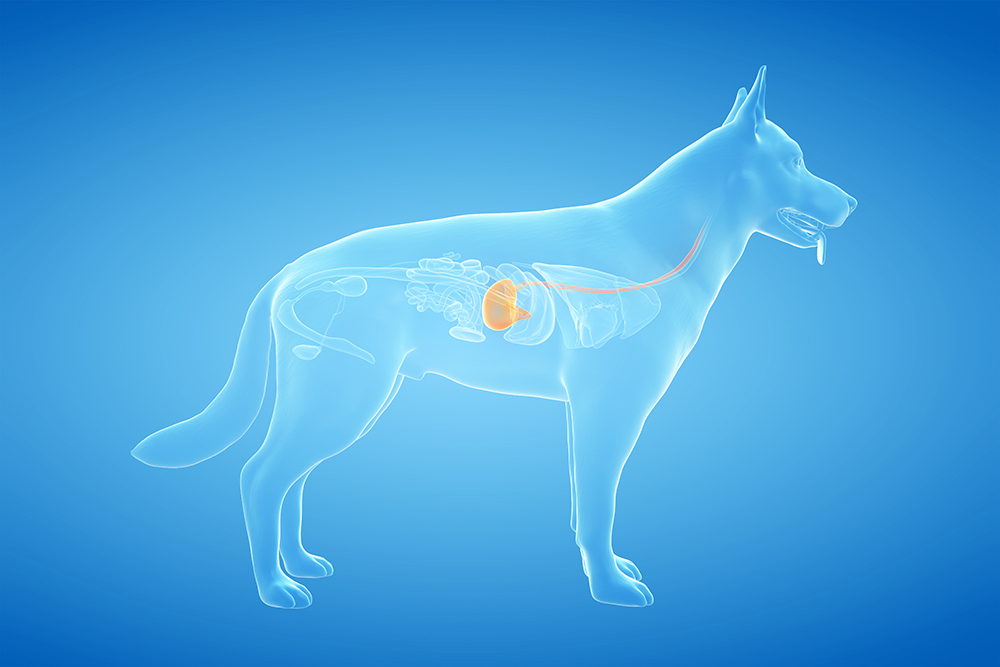

Maagdraaiing

Een maagdraaiing, ook wel maagtorsie, maagkanteling of volvulus genoemd, is een onder veel hondeneigenaren gevreesde aandoening. Bij dit syndroom vindt door nog onbekende oorzaken een abnormale ophoping van voedsel en gas plaats in de maag (dilatatie). Dit kan resulteren in een draaiing van de maag (volvulus).

De aandoening komt vooral voor bij honden van middelbare tot oudere leeftijd en dan vooral bij grote hondenrassen met een diepe borstkas. Dit betreft bijvoorbeeld de Duitse Herder, Duitse Dog, Ierse Setter en Weimaraner. Het kan echter ook gezien worden bij kleinere hondjes met een relatief diepe borstkast zoals de teckel.